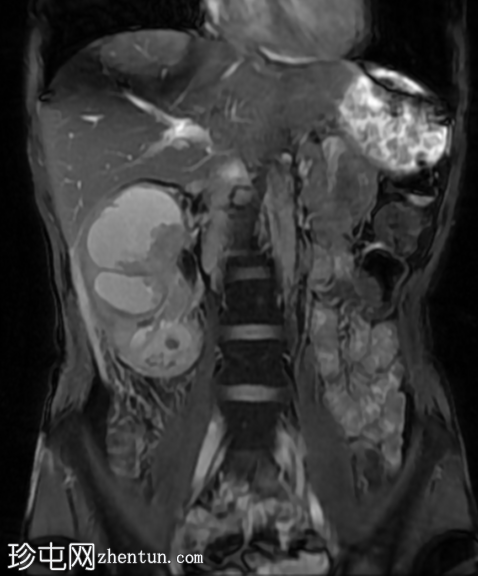

MRI

冠状位

T2加权像

再次观察到上述肾前部外生性病变,其实性成分在T1加权像上呈等高信号,在T2加权像上呈低信号,伴有碎片扩散受限和低ADC值(化脓性物质)。囊性成分内部可见液-碎片/脓液界面。可见内部低信号结石。可见肾周模糊影。该病变压迫并可能侵犯右肾盂,导致中度肾积水。

病灶不规则的低信号,以及液-液界面伴有碎屑(可能为化脓性物质)扩散受限和肾周模糊,再次高度提示炎症性病变(黄色肉芽肿性肾盂肾炎,XGP),而非可能性较小的肿瘤。

左肾萎缩,体积较小,内含多发低信号结石。